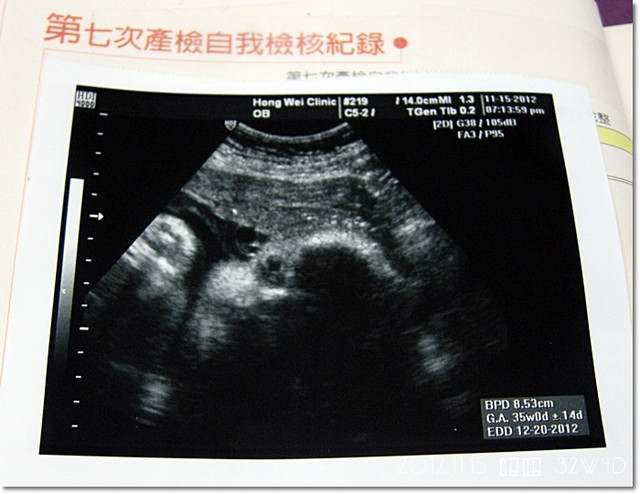

這次產檢,理論上應該是32W4D,因為上次去看妞妞的時候,是30W4D

上次預估妞妞大約是1700g,隔了2個禮拜來量了以後...

妞妞已有2300g了![]()

這次的產檢一切都正常,上次抽血做的B肝產前檢查也是正常

胎位也轉正的囉![]()